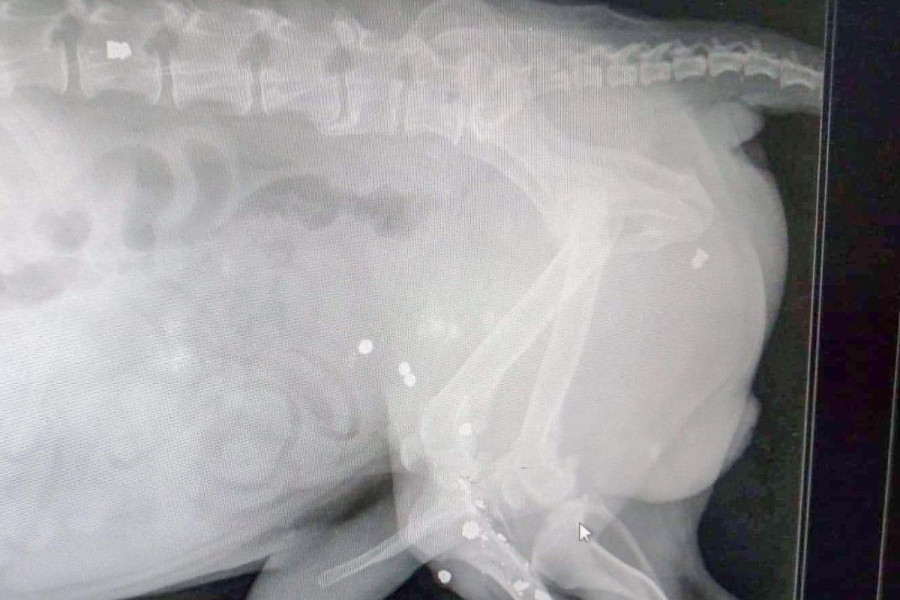

Zabrali więc Neo do weterynarza. Jak się okazało, pies został nafaszerowany śrutem przez jakiegoś zwyrodnialca. W ciele zwierzęcia tkwi co najmniej 20 kul, w tym jedna w… kręgosłupie.

Lekarz weterynarii – ze względu na wiek czworonoga – nie chce wyciągać kul, bojąc się o życie pacjenta. (Piesek mógłby po prostu nie przeżyć takiej operacji).